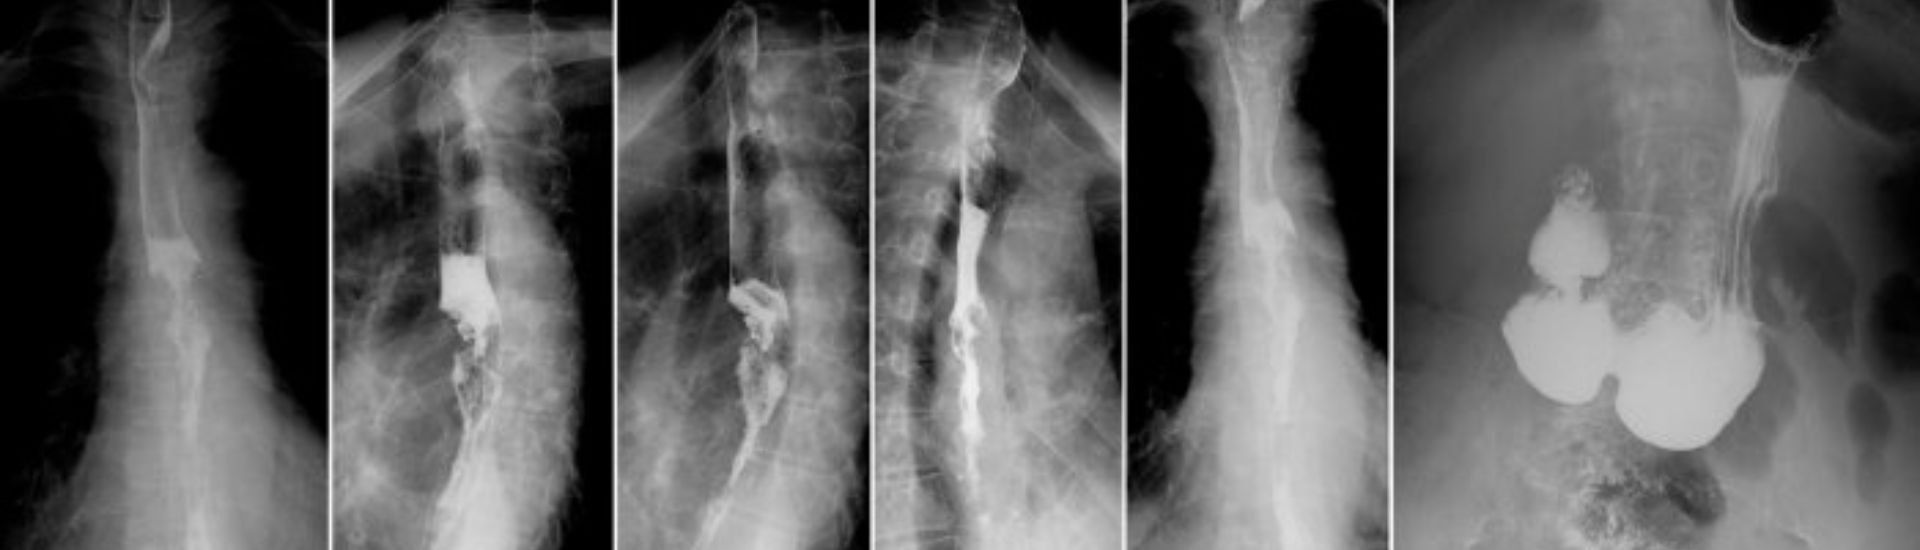

L’Esame RX Esofago con doppio contrasto è una tecnica radiologica avanzata che utilizza un mezzo di contrasto per visualizzare chiaramente le pareti dell’esofago. Questa procedura prevede l’assunzione di una soluzione di contrasto negativo, seguita dall’introduzione di aria, che permette di ottenere un’immagine nitida e dettagliata della superficie interna dell’esofago. Tale metodo è particolarmente utile per identificare lesioni e anomalie che potrebbero non essere visibili con altre tecniche diagnostiche.

Durante l’esecuzione dell’Esame RX Esofago con doppio contrasto, il paziente assume una soluzione di contrasto che aderisce alle pareti dell’esofago, rendendole visibili ai raggi X. Successivamente, viene introdotta aria nell’esofago tramite un sottile tubo, creando un contrasto che permette di osservare con chiarezza le strutture esofagee. Il radiologo acquisisce diverse immagini in varie posizioni del paziente per ottenere una visione completa dell’esofago e individuare eventuali anomalie o patologie.